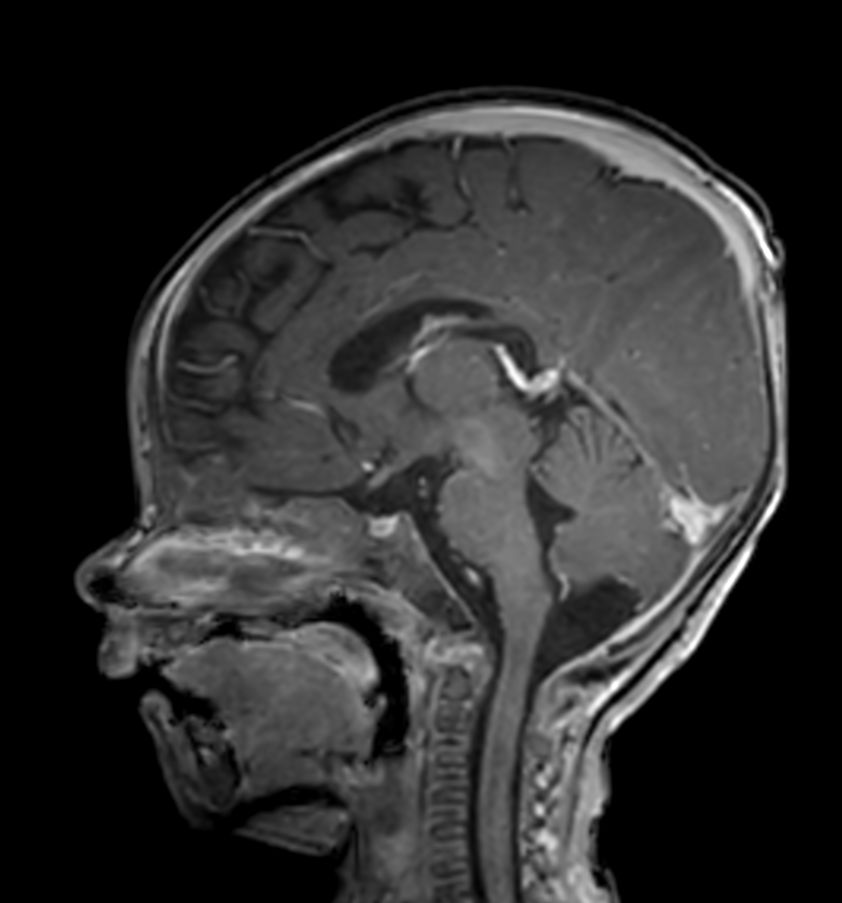

Sagittal 3D T1w TFE with ComforTone (post-gado)